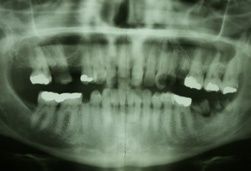

Beim ersten Termin wurde das Aufklärungsgespräch über Hypnose durchgeführt und die zu erwartenden Investitionen besprochen. Um den zu erwartenden Sanierungsbedarf einigermaßen abschätzen zu können, wurde ein Panorama-Röntgenbild (OPG) angefertigt. Nach genauer Erfragung der die Angst auslösenden Faktoren wurde ausführlich besprochen, wie die Patientin sich eine entspannte Zahnbehandlung wünscht.